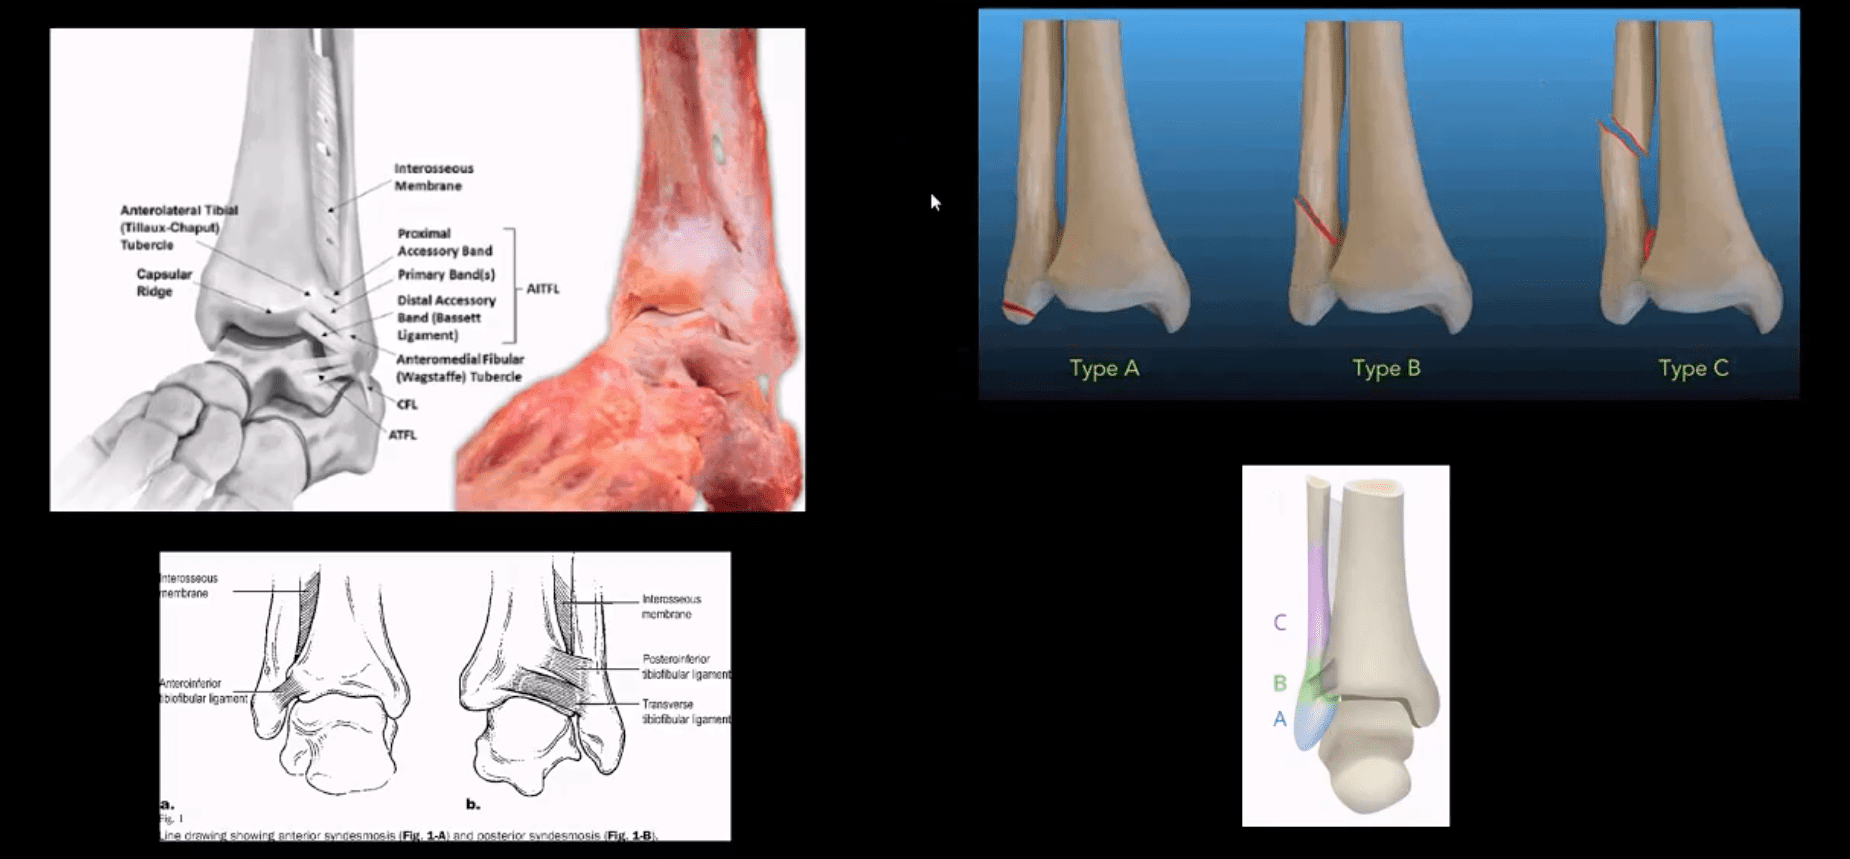

- Weber classification considers tearing of distal tibial-fibular syndesmosis and potential instability

- Weber A – below syndesmosis. Stable, typically avulsion of distal fibular malleolus

- Weber B – at the level of syndesmosis: may be outside syndesmosis and stable or tearing syndesmosis and unstable

- Weber C – above syndesmosis. Always nstable d/t tearing of syndesmosis

Tibiofibular Syndesmosis & Ankle Stability

- Denis-Weber classification of ankle fractures